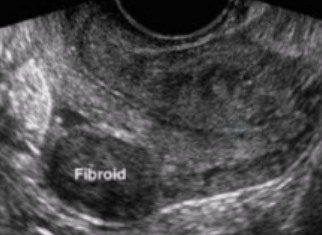

What type of fibroid is depicted in this image?

a. Intramural

b. Submucosal

c. Subserosal

d. Pedunculated

Subserosal

Where is this fibroid located in the uterus?

a. Anterior

b. Posterior

c. Cervical

d. Fundal

Anterior

Is this image endovaginal or transabdominal?

a. Endovaginal

b. Transabdominal

Endovaginal